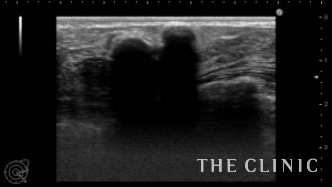

しこりが石灰化してしまうと、残念ながら切開して摘出するしか方法はありません。

しこりが気になるようでしたら、早めに受診することをお勧めします。

切開にて摘出したしこりです。